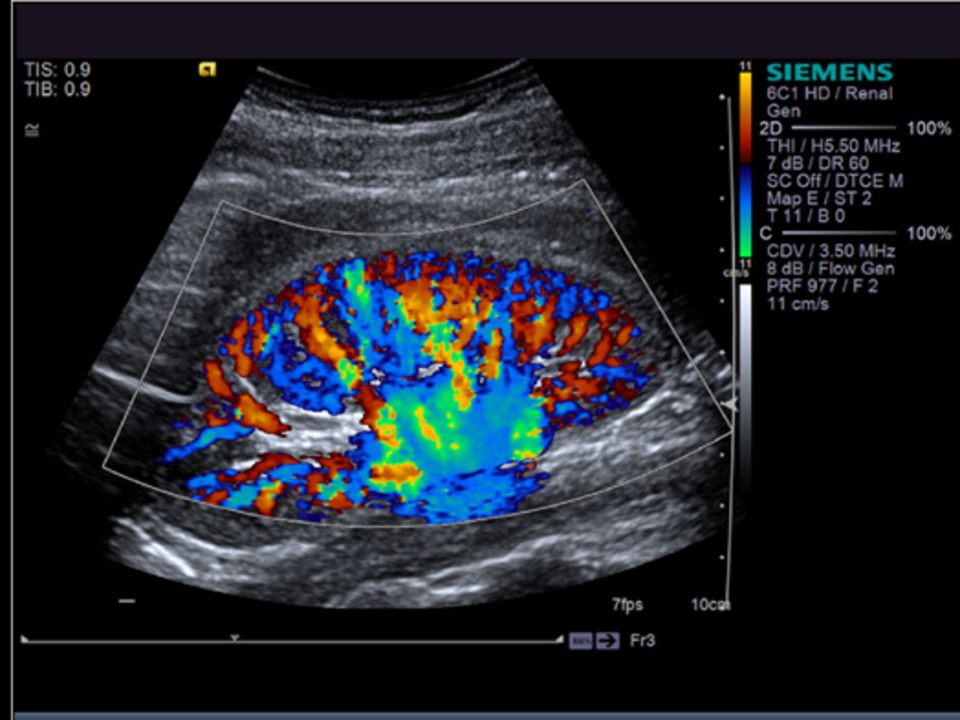

l sistema a ultrasuoni ACUSON S3000 ™, HELX ™ Evolution con Touch Control è stato progettato con un focus dedicato su Imaging generale e Radiologia interventistica. Offre nuovi livelli di efficienza del flusso di lavoro, prestazioni di imaging e sostenibilità. Il sistema è il sistema a ultrasuoni premium di Siemens che offre soluzioni esclusive, come l'imaging di elastografia, la revisione multimodale e l'ecografia a contrasto elevato.

Immagini nitide e chiare ti danno la sicurezza diagnostica necessaria per rendere la prima diagnosi quella giusta.

Può essere usato per esami quali; ecografia diagnostica, parti molli, tiroide, mammella, muscolo scheletrica, ecocolor dlopper, fibroscan, sonoelastografia